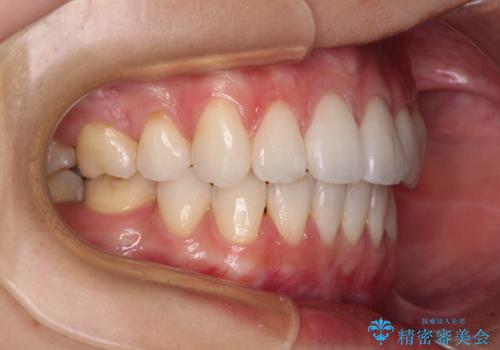

- 八重歯と口元の突出感を気にして来院された患者様です。

歯列が前方に突出しており、上下の正中がズレていたため、左側は上下第一小臼歯を、右側は上下第二小臼歯を抜去し、ワイヤー装置による矯正治療を行うこととしました。

当初はインビザラインによる矯正治療をご希望でしたが、正中を合わせたいことや、口元の突出感を改善したいことから、ワイヤー矯正を強く推奨しました。

治療期間は2年に満たず、スッキリとした口元に仕上がりました。